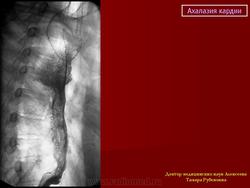

Ахалазия

• ахалазия

Случай 12: с знаком клюва птицы